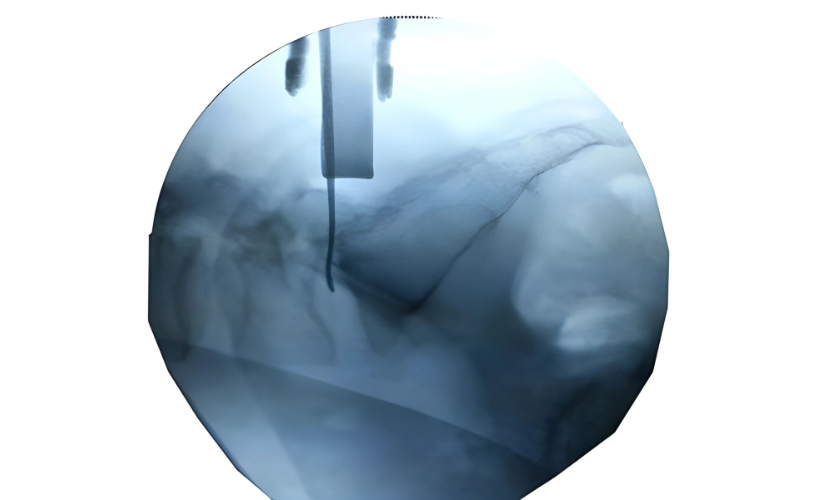

Traditional surgery to access the pituitary gland required a craniotomy (opening the skull). However, with the advancement of endoscopic transnasal surgery, this procedure can now be performed through the natural nasal passage — avoiding any external incisions.

Once diagnosed, Dr. Rahul Gupta and his multidisciplinary team — including endocrinologists and neuro-ophthalmologists — create a personalized treatment plan. For most pituitary tumors, endoscopic transnasal surgery is the gold-standard approach. Through one of the nostrils, a thin endoscope equipped with a high-definition camera provides a magnified view of the tumor area. Using specialized microsurgical instruments, the tumor is carefully removed through this corridor without disturbing surrounding brain tissue.

This technique allows for excellent tumor clearance while minimizing trauma. In some cases, where the tumor is very large or extends into the cavernous sinus, a staged or combined approach may be used. If the tumor produces excess hormones, medical therapy may be prescribed post-surgery to stabilize hormonal balance.